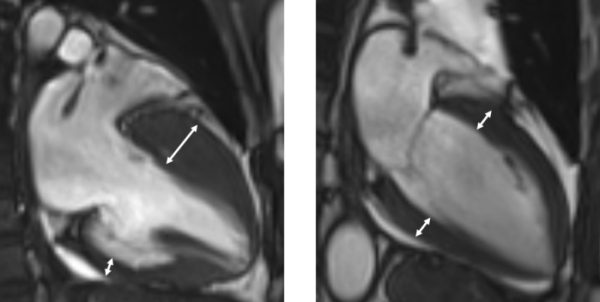

진단은 심장초음파, 자기공명영상 등 영상검사를 통해 이뤄진다. 비후된 심근 내에 섬유화가 진행돼 있거나, 근육조직이 지방조직으로 변성이 돼 있는 상태가 관찰된다. 하지만 이 같은 조직변성이 없는 비후성 심근병증도 있는 만큼 전문의의 종합적 판단이 중요하다.